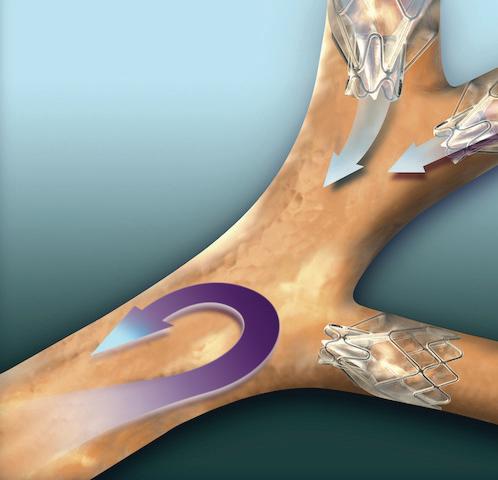

Now Monmouth Medical Center (MMC) is the first hospital in the region to offer Zephyr Valves, a new lung valve treatment. Zephyr Valves received breakthrough device designation and were approved by the Food and Drug Administration in 2018 to help patients with severe COPD and emphysema breathe easier without many of the risks associated with major surgery.

RELIEVING PRESSURE

Emphysema triggers extreme shortness of breath as air becomes trapped in parts of the lung damaged by the disease. Airfilled damaged areas become larger—a condition called hyperinflation that puts pressure on the diaphragm and makes breathing difficult.

With treatment using Zephyr Valves, a physician places an average of four valves to occlude airways leading to the targeted, hyperinflated part of the lung in a procedure that usually takes under an hour. The valves allow excess air to escape while blocking airflow into the treated area. Healthier parts of the lungs expand, relieving pressure, decreasing shortness of breath and allowing better breathing. Benefits have been shown to last at least one year after valve implantation.

“Prior to the introduction of this technology, the only treatment options for patients who failed nonsurgical options such as pulmonary rehab were highly invasive treatments including lung

reduction and lung transplant surgeries,” says Richard Lazzaro, MD, Southern Region Chief of Thoracic Surgery, who treats patients at MMC and MMCSC and is teaming with MMC on the Zephyr program. “This breakthrough treatment is going to help us restore quality of life to so many residents in our region who struggle with breathing due to severe emphysema.”